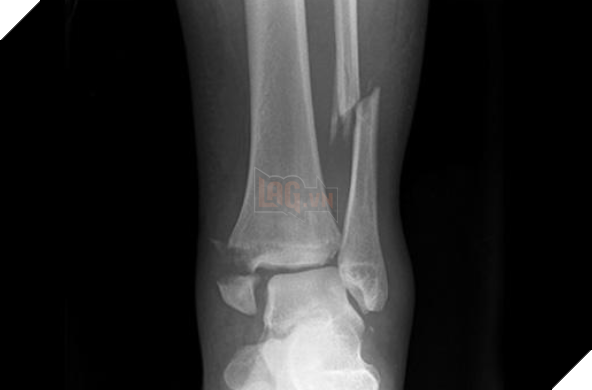

Tuy nhiên không phải ai cũng có thể tập luyện một cách suôn sẻ được, bởi cách đây không lâu thì đã có một thanh niên người Malaysia đã bị gãy cổ chân bởi mong muốn thực hiện được "thử thách Saitama" và vượt qua được giới hạn của bản thân mình.

Nhưng với cường độ vận động quá mạnh như vậy đã khiến cho cơ thể của một người bình thường không chịu nổi, hậu quả là anh đã bị gãy cổ chân và phải nằm dưỡng thương suốt 8 tuần lễ. Đây có lẽ là một bài học mà những người muốn tập luyện như Saitama phải xem xét, bởi tập luyện là một điều tốt, nhưng tập luyện quá sức mà không nghỉ ngơi một cách khoa học sẽ dễ gặp phải những chấn thương đáng tiếc.